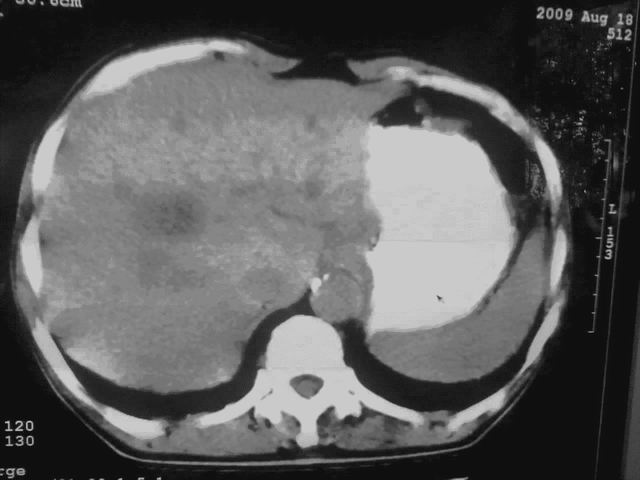

我这个考考大家眼力,看看是升结肠ca还是降结肠ca

好象是横结肠占位肝转移,胰头占位?【伙计,您的片也真够意思】

横结肠占位肝转移

伪影太多,考虑降结肠癌伴肝转移,胆囊炎

伪影太多,考虑升结肠癌伴肝转移,胆囊炎

考虑升结肠癌伴肝转移;胆囊炎。

结肠占位并肝及腹膜后淋巴结转移。

考虑升结肠癌伴肝转移;胆囊炎